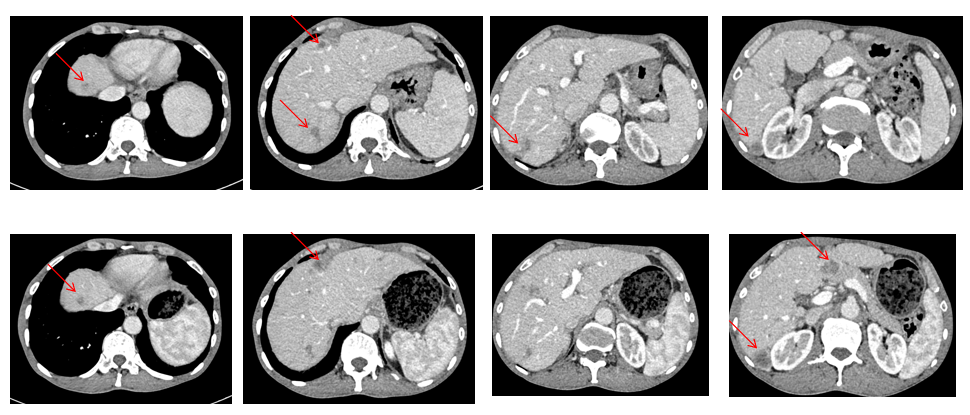

2025年1月复查,腹部CT提示肝脏部分病灶较前略有增大(图3)。

此时调整方案为“维迪西妥单抗+信迪利单抗”双药联合,治疗4周期后评估为疾病进展(PD)。